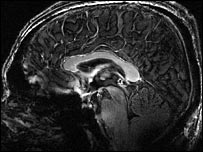

| Click here to see the brain scan in greater detail

First, I was scanned inside a top-of-the-range three tesla magnet. These MRI scanners are used in research and some hospitals. I then spent about 40 minutes inside the new 7T scanner.

It promises the most detailed images yet of the brain, as well as intricate real-time imaging of thought processes that can be used to study mental illnesses such as schizophrenia.

Even to my untrained eye, I could see the stark contrast between the new and the old.

The seven tesla image was crisper, with far more detail.

"Essentially what we are seeing with the seven tesla is an amplified difference between the different tissues, and with much finer resolution, so we can see much finer detail," said Professor Morris.

"We can look down at a lower scale than we have been able to before. We know that there are some lesions which are located within particular structures which are currently too fine to see, and we hope we will be able to address those at seven tesla.